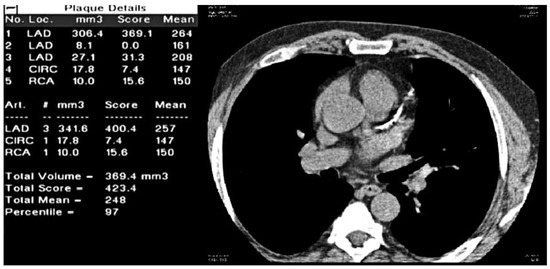

Purpose: To compare the effectiveness of assessment tools for 10-year cardiovascular risk in physician-referred Swiss patients. Material and Methods: The risk evaluation according to the Prospective Cardiovascular Münster algorithm, adapted for the Swiss population (CH-PROCAM) was defined as PROCAM corrected by [...] Read more.

Purpose: To compare the effectiveness of assessment tools for 10-year cardiovascular risk in physician-referred Swiss patients. Material and Methods: The risk evaluation according to the Prospective Cardiovascular Münster algorithm, adapted for the Swiss population (CH-PROCAM) was defined as PROCAM corrected by the factor 0.7 for Switzerland in all subjects ≥50 years of age and 0.18 in women <50 years in age. In these subjects, CH-PROCAM, the algorithm of the European Atherosclerosis Society (EU-SCORE), coronary calcium score percentiles (CS%), and total plaque area of the carotid arteries (TPA) were available. Posttest probabilities (PTP) for CS% and for TPA were calculated by using the Bayes formula. Agreement for starting an LDL cholesterol (LDLC)-lowering therapy between CH-PROCAM and CH-PROCAM-PTP was assessed in intermediate risk patients. Results: CH-PROCAM identified 17 (10%) and EU-SCORE 42 (24%) out of 175 individuals at high risk (p = 0.0006, weighted kappa (wK) = 0.45). CH-PROCAM-PTP identified 30 (17%) and EU-SCORE-PTP 66 (38%) individuals at high risk (p <0.001, wK = 0.26). The 19 patients with vascular disease (9% of 213) were detected by CH-PROCAM-PTP (receiver operating characteristics (ROC) 0.69, p = 0.002), but not by the other methods. Agreement to start a LDLC-lowering therapy in intermediate risk subjects was moderate (wK = 0.54). Conclusion: CH-PROCAM classified patients at high risk significantly less often than EUSCORE. EU-SCORE-PTP appears to substantially overestimate the true risk. What is most important, CH-PROCAM-PTP identified patients with clinical vascular disease, as shown by ROC analysis. Therefore, CH-PROCAMPTP currently represents a valuable method for further stratifying risk in primary care patients who have been defined by CH-PROCAM as being at intermediate risk, and may be helpful to correctly identify subjects who deserve an LDL lowering therapy. Full article

Figure 1